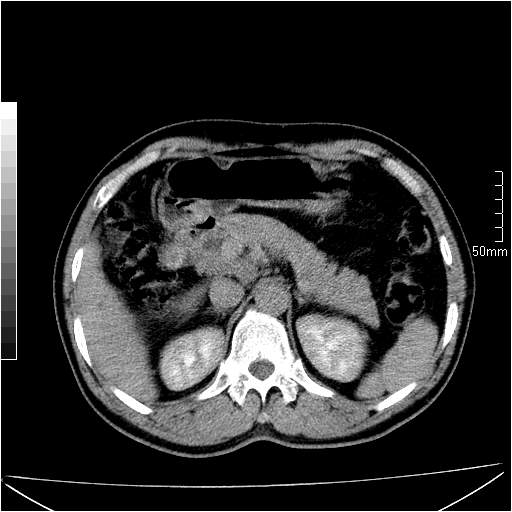

男性,54岁,皮肤黄染,搔痒一周余.b超示肝左叶回声异常.初步诊断1胆总管下段结石2胆囊结石伴慢性胆囊炎请各位战友帮忙看一下肝脏多发低密度如何解释恰当.增强效果不是很好.请大家见谅.

首先,胆总管下端结石梗阻伴肝内胆管扩张可确定。

另外,肝八段低密度占位,呈多灶性,考虑肝脓肿或肝癌可能,(图像质量欠佳)建议进一步检查。

既然做了增强,为什么光提供延时期片子,肝动静脉期肝右叶前下段病灶增强如何?另外胆囊壁增厚,欠规整,内密度不均,与肝右叶病灶分界不清,增强表现怎样?肝内胆管轻度扩张,胆总管扩张,但未见明显结石影,也应提供增强早期图像才好鉴别扩张原因。片子较清,但不够完整,暂考虑1.胆囊癌肝局部浸润,或肝癌胆囊侵犯,2.胆总管下端或胰头钩突部占位。总之本人看不明白,请高手画图指示,先谢了!

由于胆囊窝内结构显示不清,肝脏病灶又邻近胆囊窝首先考虑胆囊癌肝受侵犯。而后因肝脏病灶强化有渐进改变,且相邻胆管扩张,故考虑肝胆管细胞癌待排。

左肝胆管细胞癌。

胆总管下端结石。